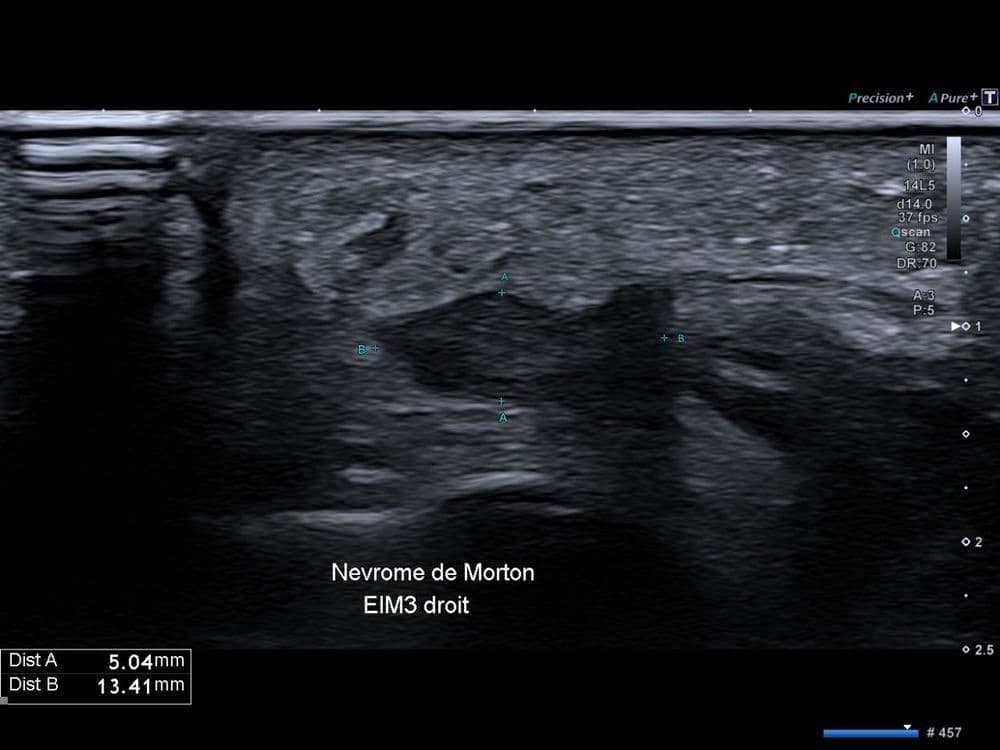

Métatarsalgie centrale non traumatique chronique du 3ème espace inter métatarsien.

US